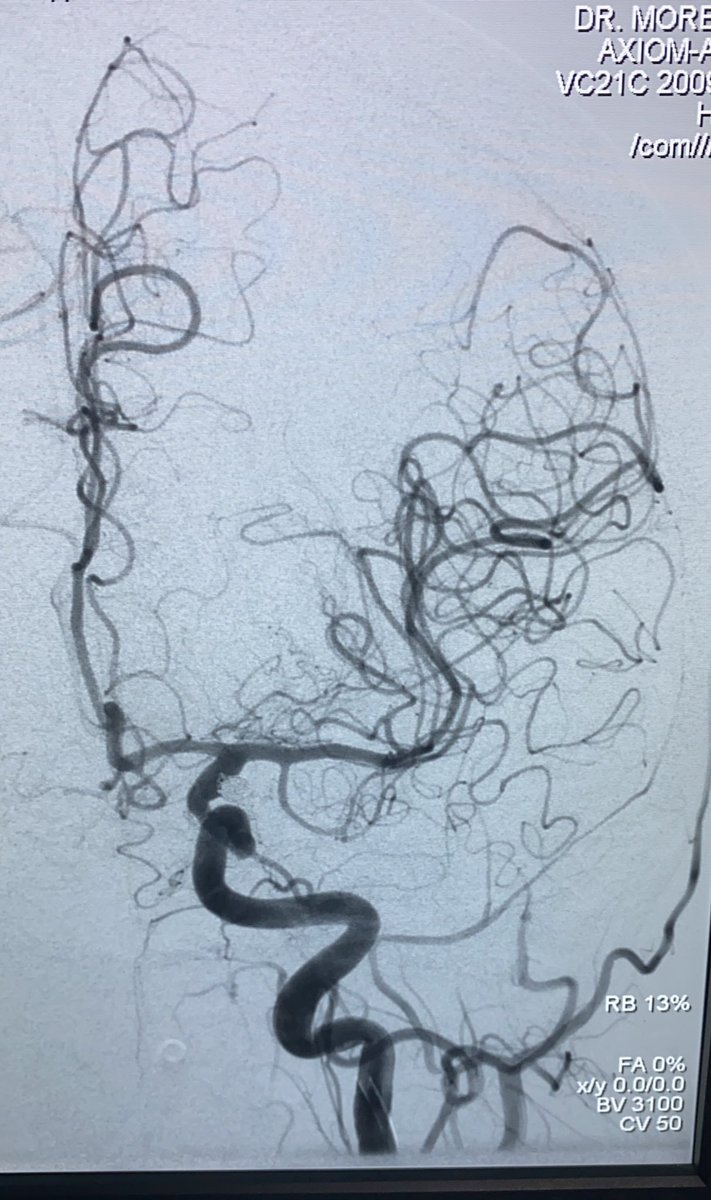

Ceki Sagiz, especialista de producto de BALT, nos explica las posibles soluciones endovasculares a un aneurisma de bifurcación de arteria cerebral media derecha. #tratamientoendovascular #middlecerebralartery #aneurysm m.youtube.com/watch?time_con…